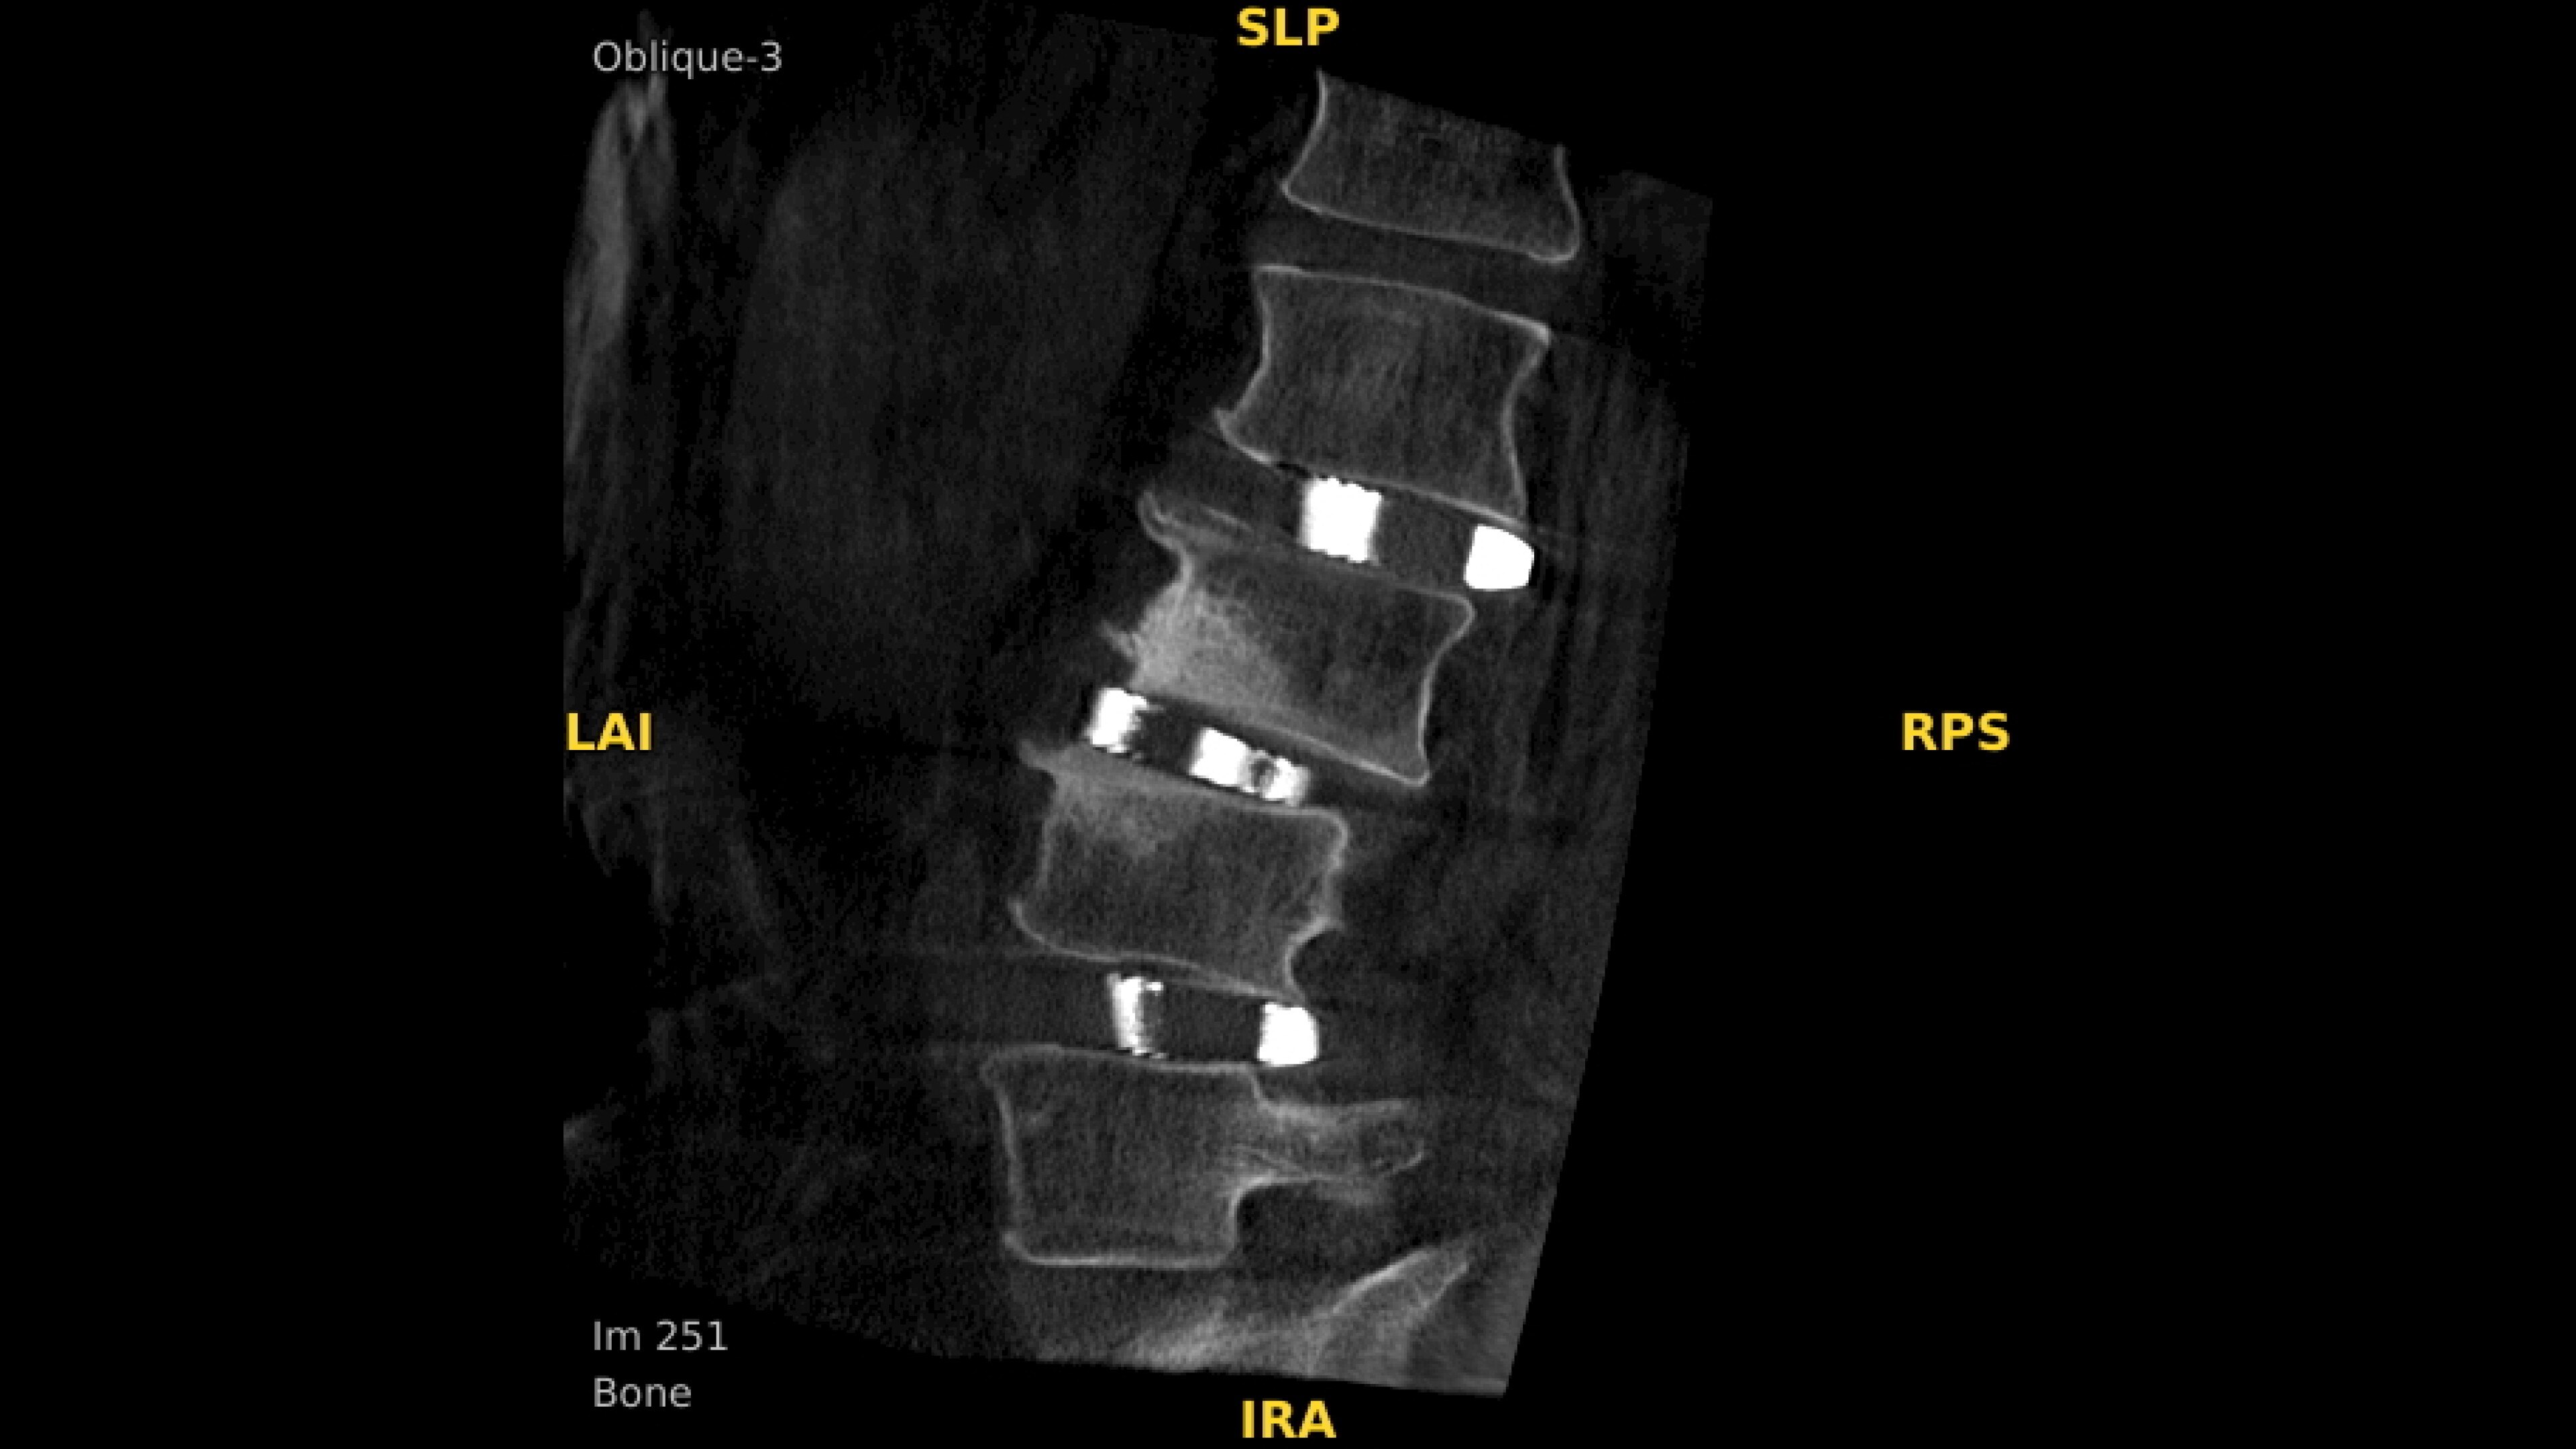

Analyze CT-like images with the OEC 3D Volume Viewer which includes Multi-Oblique, Area Measure, Window Level/Window Width, rotate, zoom, and more for quick and comprehensive visualization.

Enhance 2D imaging with Spine and C-Spine preset profiles. Digitally zoom up to 4X during a fluoro shot with no change in dose by using Live Zoom.